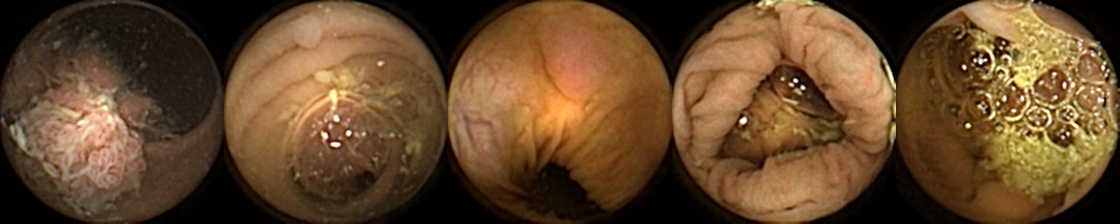

Figure 3 shows classification output examples for the MIV model using the pretrained ConvNext. Note that the model has a test accuracy of 83.66% for DBA L2 with 2 heads. In each row, the leftmost image is the query and the four images to the right of each query are the target images. The True Positive (left-top) and True Negative (bottom-right) examples outline the cases when the model is able to successfully distinguishes images containing unique polyps from those with dissimilar polyps. The False Negative (top-right) and False Positive (bottom-left) examples show the cases where the model fails to correctly distinguish images of unique polyps and images of dissimilar polyps. Further, we can note from the differences in the examples of True Positives and False Negatives that when the query image and the target set instances differ from each other in some ways, then the model can misclassify images. These differences could be attributed to different views due to the dynamics of the camera inside the colon, different views from two camera heads of the capsule, or presence of artifacts such as bubbles, debris, and small bowel secretions.

On the other hand, when we look at the examples of False Positives (Pred = true, Label = false) in Figure 3, we can note that if images in the target match the query in ways such as texture, color, illumination conditions, presence of artifacts, then this may lead to misidentification of the query as belonging to the targets. For True Negative (Pred = false, Label = false) examples, we can see that presence of significant differences between the query and the targets leads to correct identification of the image sets as different.

True Positive False Negative

False Positive True Negative

Figure 3: True Positives (Pred = true, Label = true), False Negatives (Pred = false, Label = true), False Positives (Pred = true, Label = false), True Negatives (Pred = false, Label = false) for the DBA L2(h=2) model using the pretrained ConvNeXt. In each row, the leftmost image is the query and the 4 images to the right of each query are the target images.